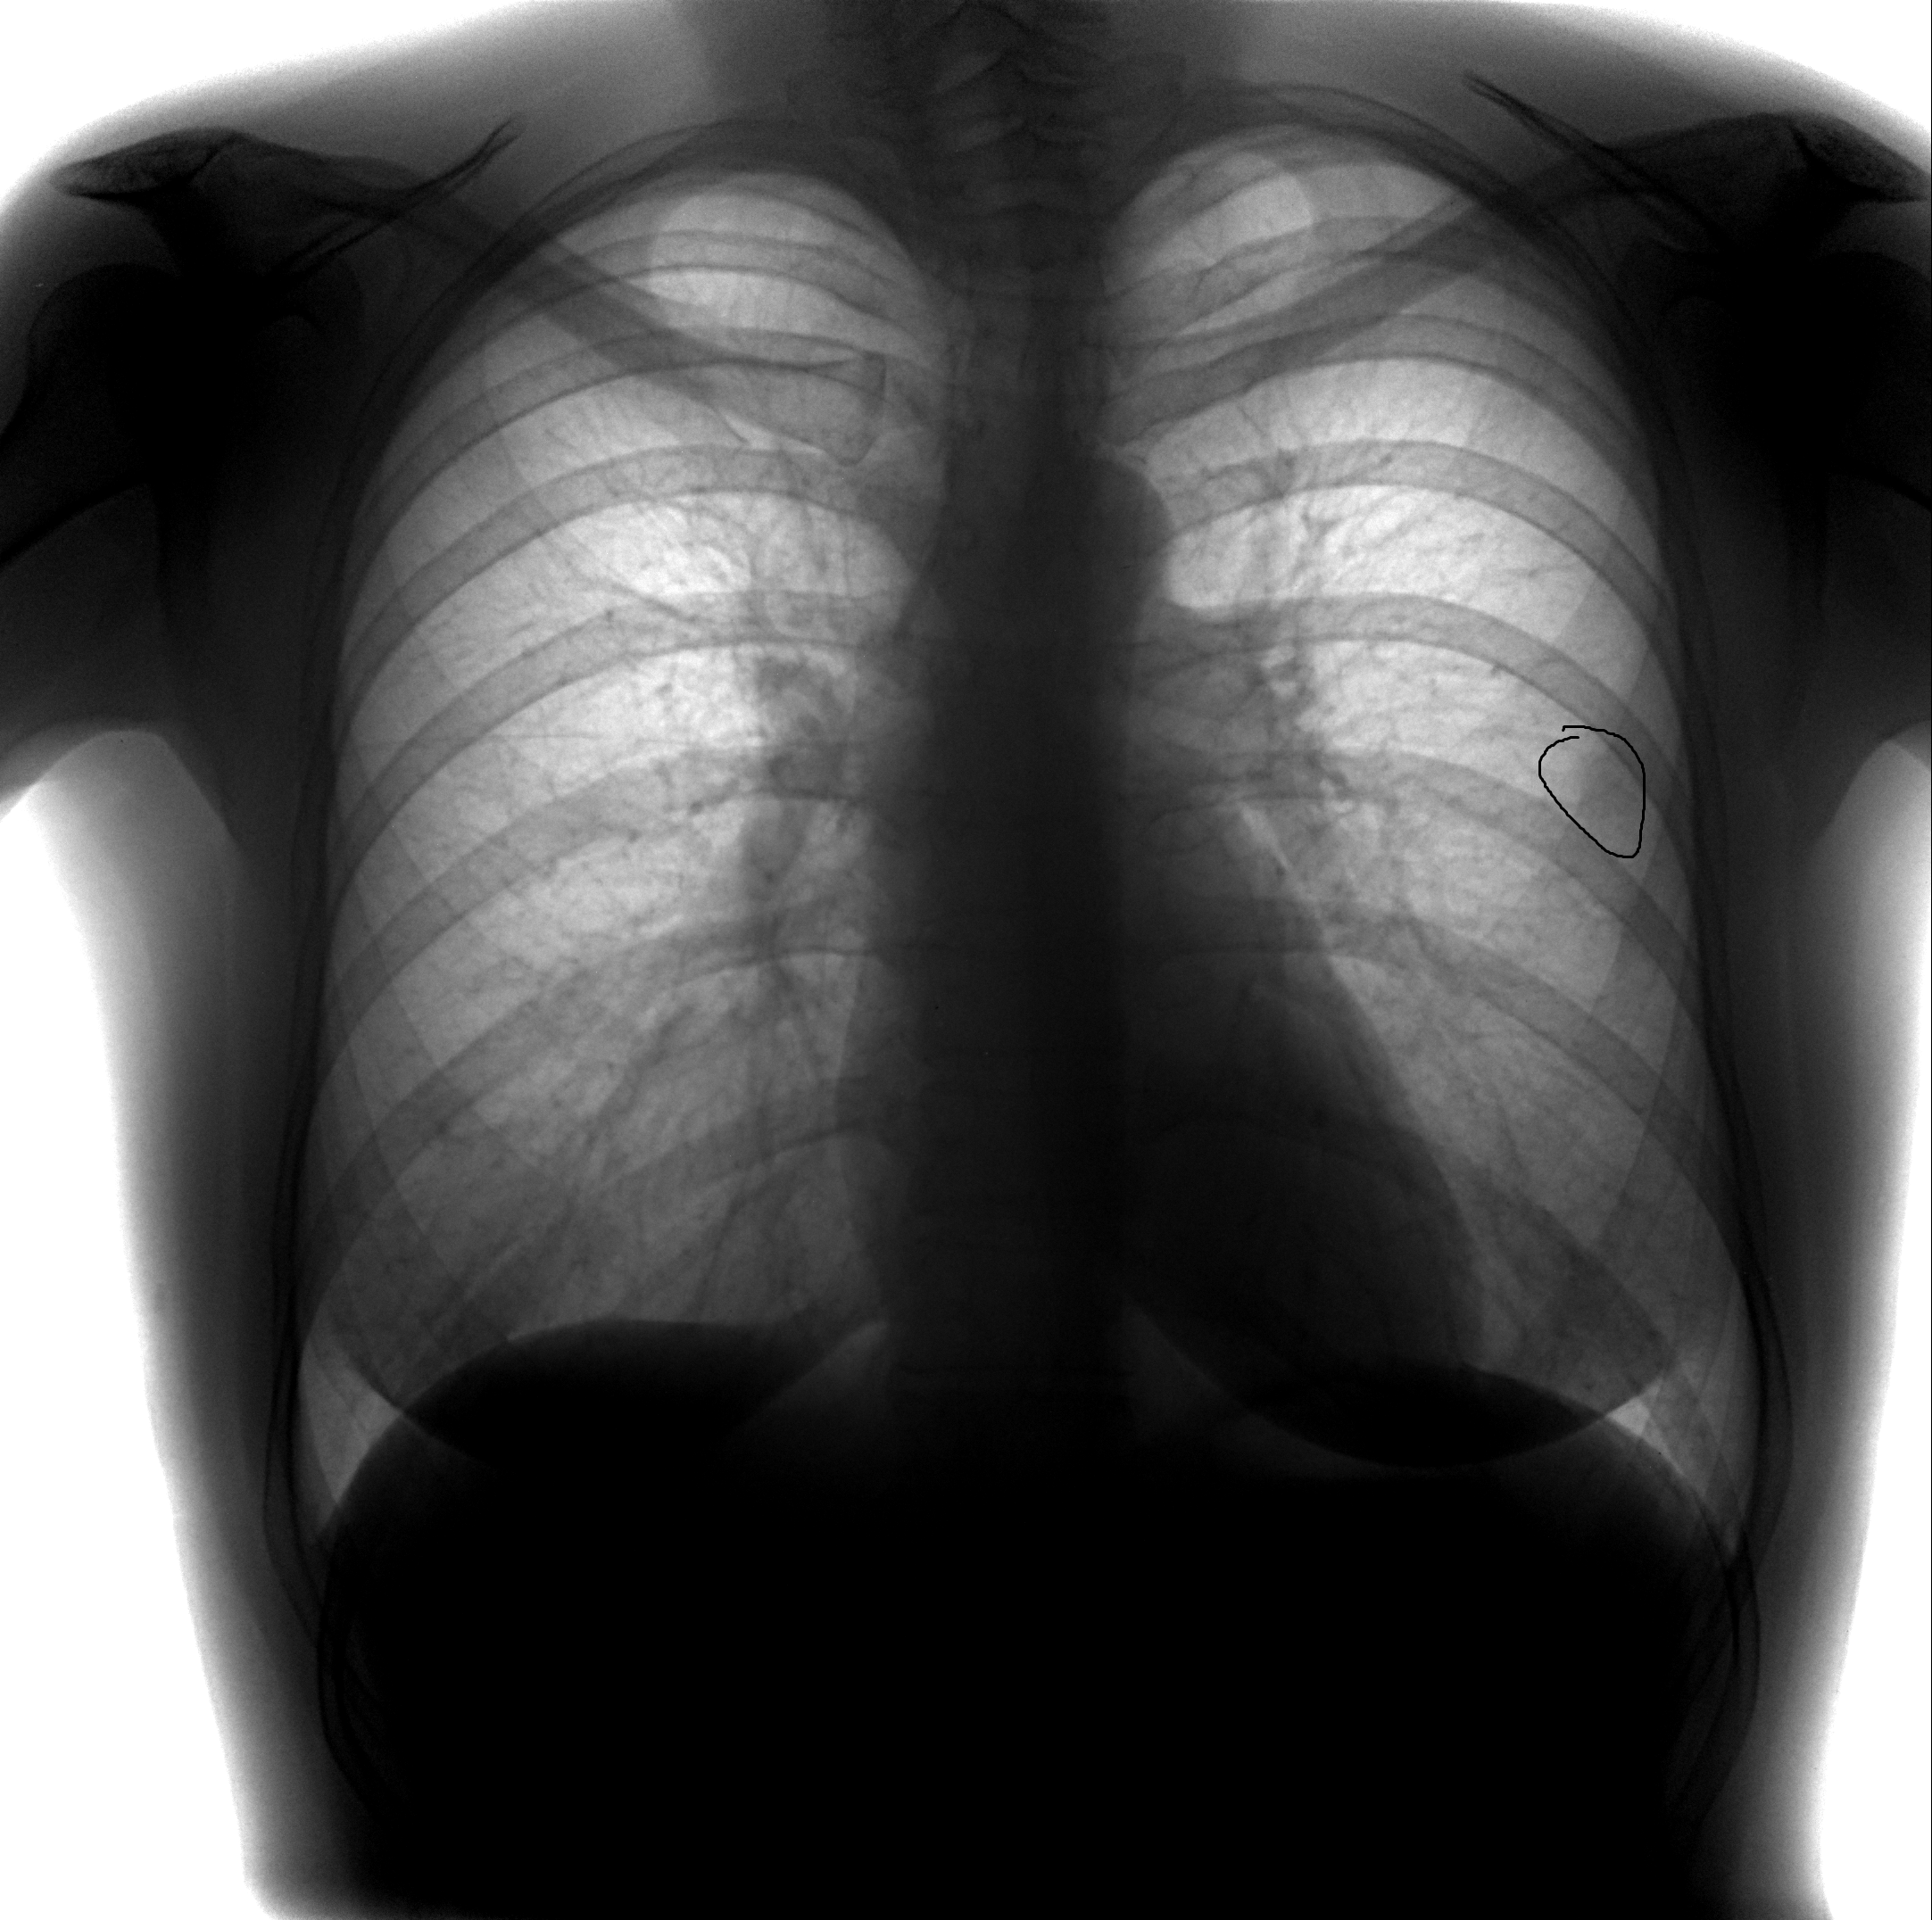

Рентген здоровых легких: примеры снимков и советы

Раздел: Сокровищница опыта